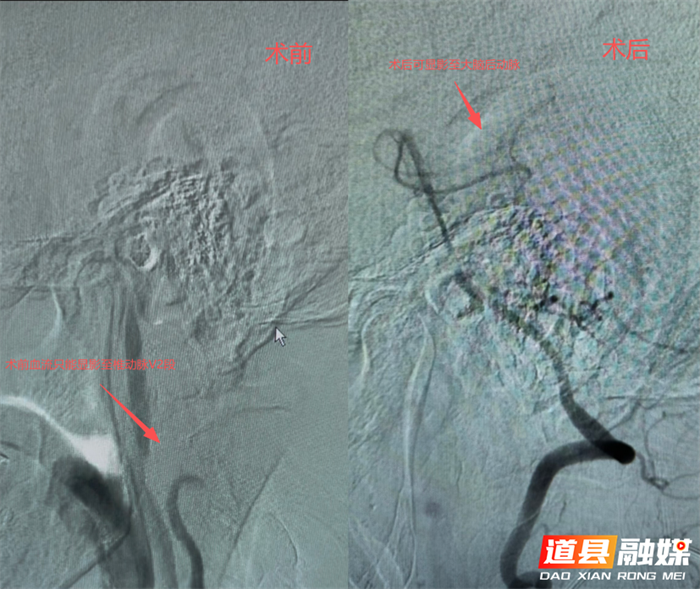

手术过程中,中风科介入团队在DSA(数字减影血管造影)引导下,精准穿刺患者股动脉,首先为患者进行狭窄部位造影,选取最好的工作角度,精准操控导丝、导管顺利通过狭窄病变血管,并依次完成球囊预扩张,运用“球囊穿梭”技术送高导引导管,再以“特洛伊木马”技术输送支架至血管狭窄处,支架精准定位与释放,全程操作精准流畅。术中实时造影可见狭窄部位程度改善,患者锁骨下动脉狭窄段完全扩张,支架位置精准、贴壁良好,血流通畅,盗血现象即刻消失,双侧上肢血压恢复对称,手术圆满成功。